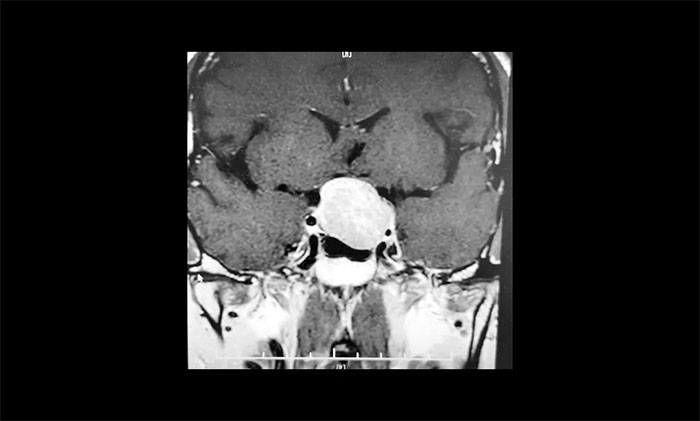

▲ 肿瘤侵袭生长,包绕左侧海绵窦

为求进一步确定病情,张先生在家人陪伴下,慕名来到上海蓝十字脑科医院。经鞍区MRI平扫+增强显示:蝶鞍显著扩大,鞍底下陷,垂体窝见类椭圆形异常信号,大小约3.1×2.7×2.1cm,病变向鞍上生长,推移视交叉上抬,与左侧海绵窦分界欠清晰,被包裹1/2。

神经外科6B病区专家李士其教授、潘仁龙主任、吴治群博士会诊后,考虑为侵袭性垂体巨腺瘤,乒乓球大小的瘤体压迫视神经,并且侵袭生长,左侧海绵窦部分受包绕,向上已突破鞍隔,压迫视神经、视交叉、下丘脑。如果肿瘤进一步生长,可能加重视力下降、甚至失明。